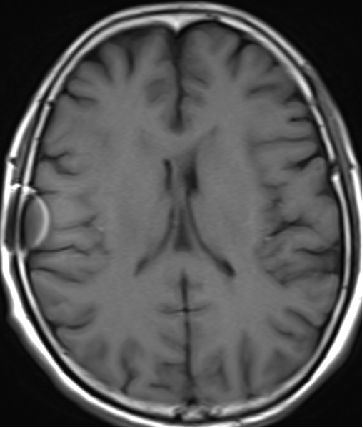

2014-10-17 CT

仍时有前额部疼痛,程度轻,调压190—200